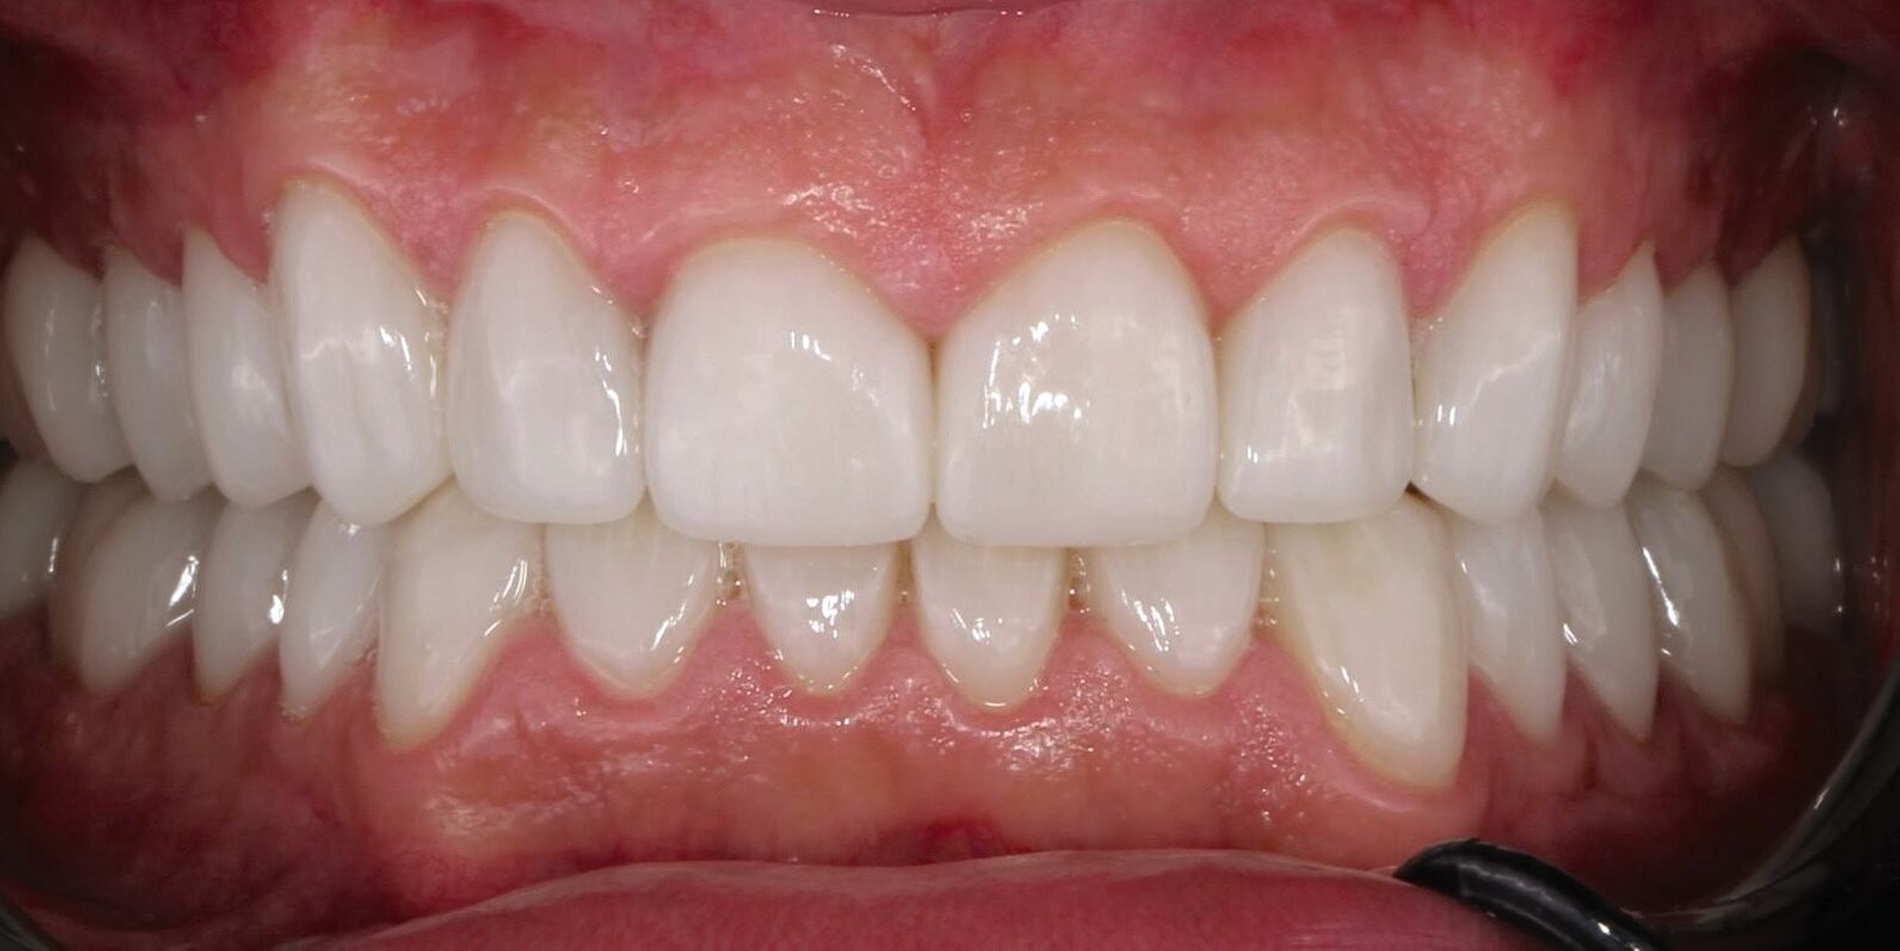

Da der Patient mit der Situation zufrieden war, konnte nach einigen Wochen die endgültige Versorgung bestehend aus Lithiumdisilikat-Kronen (e.max®, Ivoclar, Schaan, Liechtenstein) adhäsiv mit einem dualhärtenden Befestigungskomposit (RelyXUltimate™, 3M™, Neuss) eingesetzt werden. Der Patient bekam außerdem eine Unterkiefer-Aufbissschiene mit adjustierter Kaufläche für die Nacht.

Fazit

Der Patient konnte vollständig saniert werden und kam mit der neu eingestellten Bisshöhe sehr gut zurecht. Während der Behandlung wurden Ernährungshinweise gegeben, um die langfristige Haltbarkeit der Restauration zu gewährleisten. Eine besondere Herausforderung stellten in diesem Fall der angestrebte Ausgleich der verlorenen vertikalen Höhe und die Bestimmung der Myozentrikposition dar.